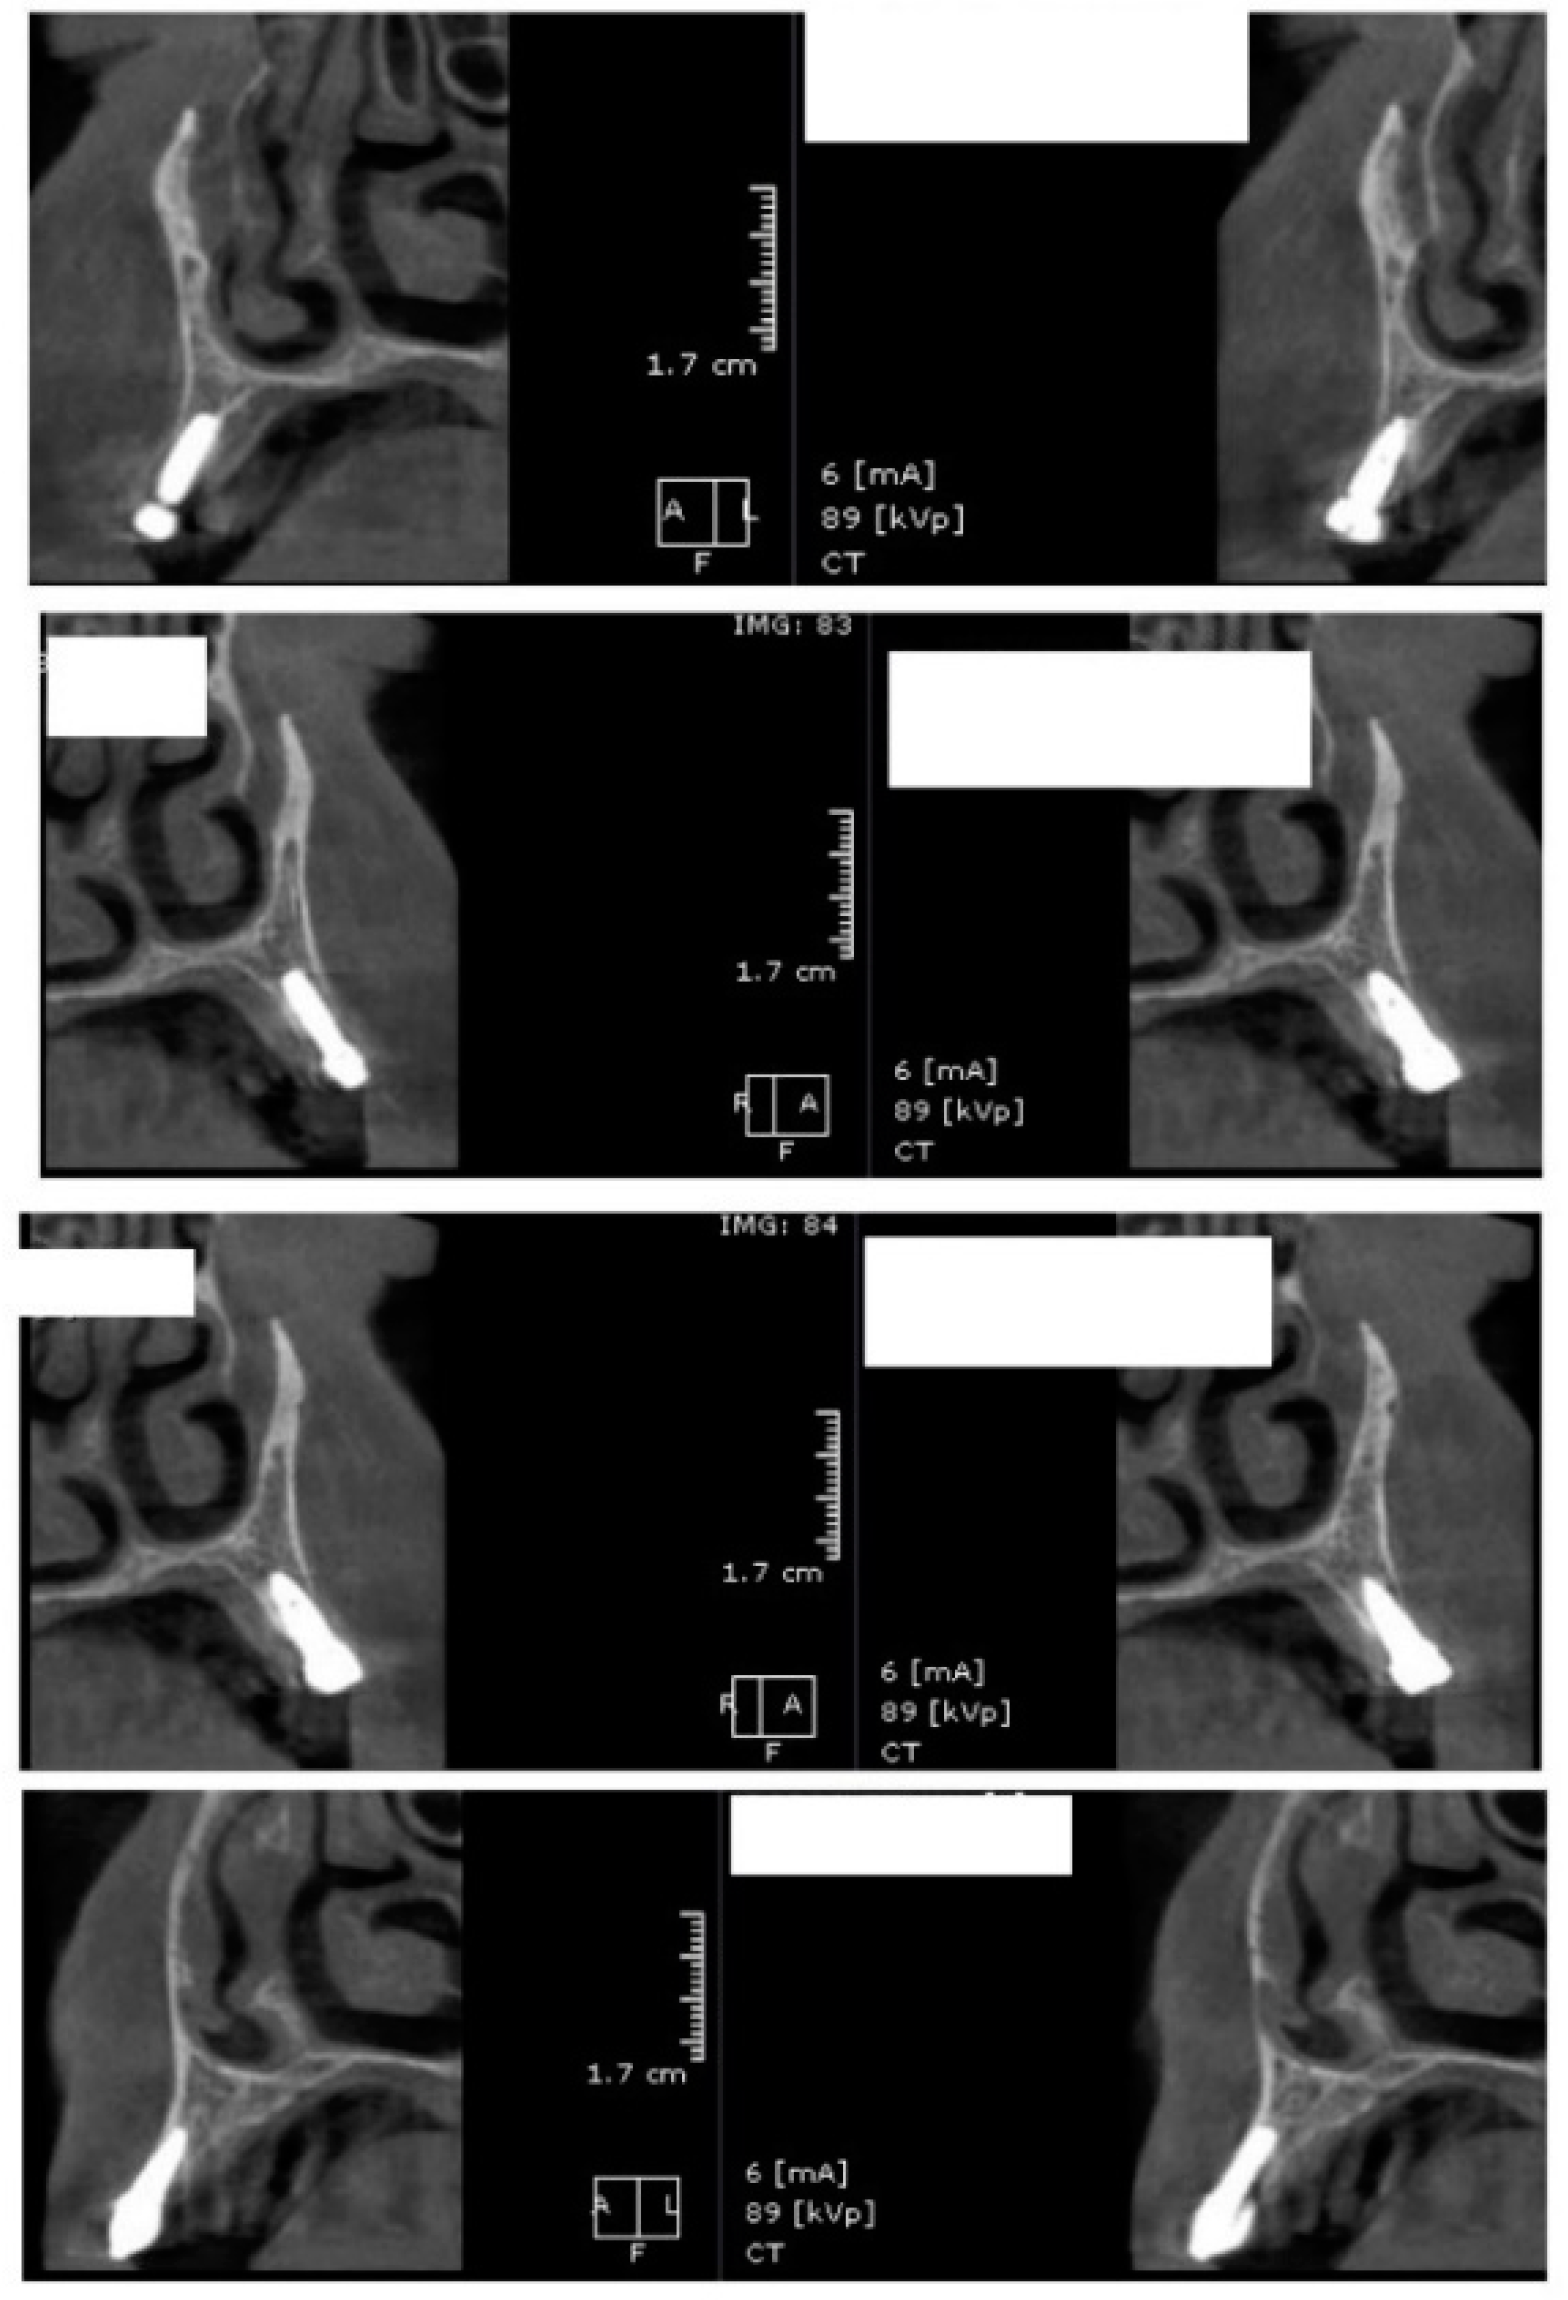

In the subsequent stage of the study, the clinical objectives were met, namely the determination of the radiological bone level, width, height and bone density on Cone Beam Computed Tomographyscans (Planmeca™, Helsinki, Finland). CBCT images were recorded using a tube voltage of 89 kV and a current intensity of 6 mA, the images were recorded with a cylindrical field of view (FOV) of 82 mm both in diameter and height (Figure 1), the voxel size was 0.2 × 0.2 × 0.2 mm and the dental arches were positioned similarly in the FOV, as presented in Figure 2.

Figure 1.

The field of view was a cylinder of 82 mm in diameter and height. The left panel is a 3D section CBCTCone Beam Computed Tomography image, whereas the right panel represents an oblique-section of the same image. F, frontal view, A, Axial View, R, right side view.

For image acquisition, we used a ProMax 3D CBCT unit (Planmeca, Helsinki, Finland), with the previously mentioned settings. Images were acquired and saved in JPEG format. To locate implant target sites, bone density, and to record the mean CT number of the trabecular bone from these sites, we used the OnDemand 3Ddata App™ software (Cybermed Inc., Seoul, South Korea). In each site, our region of interest was a square volume of bone located within the alveolar ridge (Figure 3, Figure 4 and Figure 5). All data recorded were input into the Microsoft Office Excel™, 2017 version, analysis software (Microsoft, Redmond, WA, USA).

Figure 3.

CBCT images used in the study, showing sagittal sections of bone.